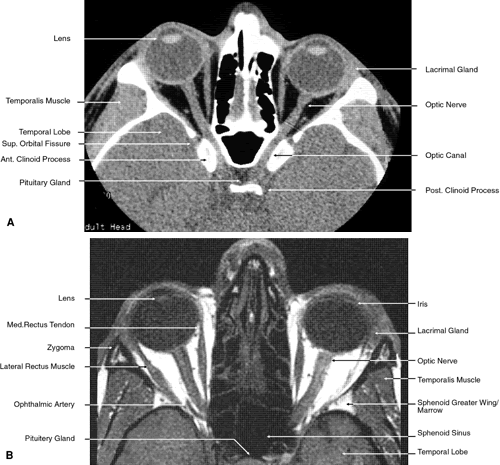

Fig. 17. Coronal images through anterior orbit. A. Computed tomography scan. B. T1-weighted magnetic resonance imaging.

Fig. 18. Coronal images through midglobe. A. Computed tomography scan. B. T1-weighted magnetic resonance imaging.

Fig. 19. Coronal images through midorbit posterior to the globe. A. Computed tomography scan.B. T1-weighted magnetic resonance imaging.

Fig. 20. Coronal images through orbital apex. A. Computed tomography scan. B. T1-weighted magnetic resonance imaging. C. Anatomic section of a cadaver head at the level of the orbital apex.

Fig. 21. Coronal images through optic canal. A. Computed tomography scan. B. T1-weighted magnetic resonance imaging.

Fig. 22. Axial images at the level of inferior orbit. A. Computed tomography scan. B. T1-weighted magnetic resonance imaging.

Fig. 23. Axial images at the level of midorbit. A. Computed tomography scan. B. T1-weighted magnetic resonance imaging.

Fig. 24. Axial images at the level of superior orbit. A. Computed tomography scan. B. T1-weighted magnetic resonance imaging.

Fig. 25. Axial images at the level of tendon of the superior oblique. A. Computed tomography scan. B. T1-weighted magnetic resonance imaging.

Fig. 26. T1-weighted magnetic resonance imaging; sagittal image through optic nerve.